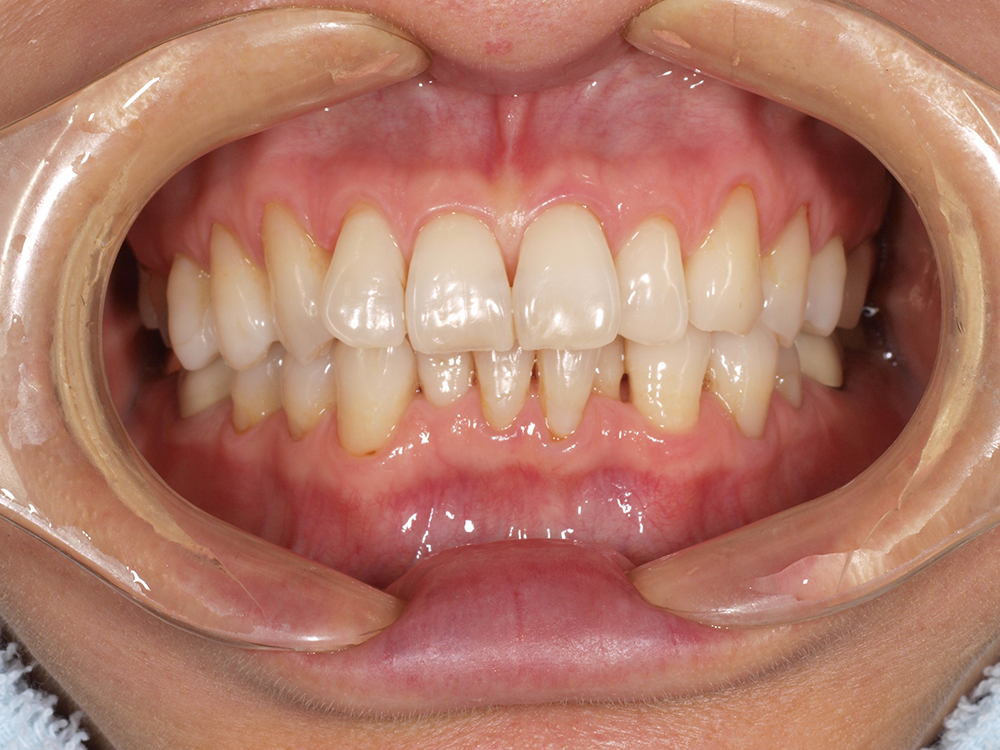

53歳 男性

- 主訴

- 全然噛めない。上の歯が取れてきた

- 処置内容

- 上顎:8本 下顎:2本

- 治療費用

- 上顎:約320万円(税込)、下顎:約160万円(税込)

- 治療期間

-

上顎:1年(仮歯まで8か月)

下顎:8か月(仮歯まで5か月)

- リスク

- 上部構造物、仮歯の破折、術後の腫れ(3日)、人工歯根脱落リスクがあります